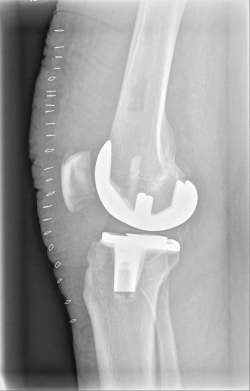

Example X-ray images before and after implantation of a Persona knee prosthesis with robot.

| b) nach Implantation der Knie-Totalendoprothese angefertigte Röntgenaufnahmen | |

With the robot-guided support, the artificial knee joint is then inserted with millimeter precision, and the required establishment of the straight leg axis in the knee joint as well as the correct rotations of the prosthetic components can then be ensured.